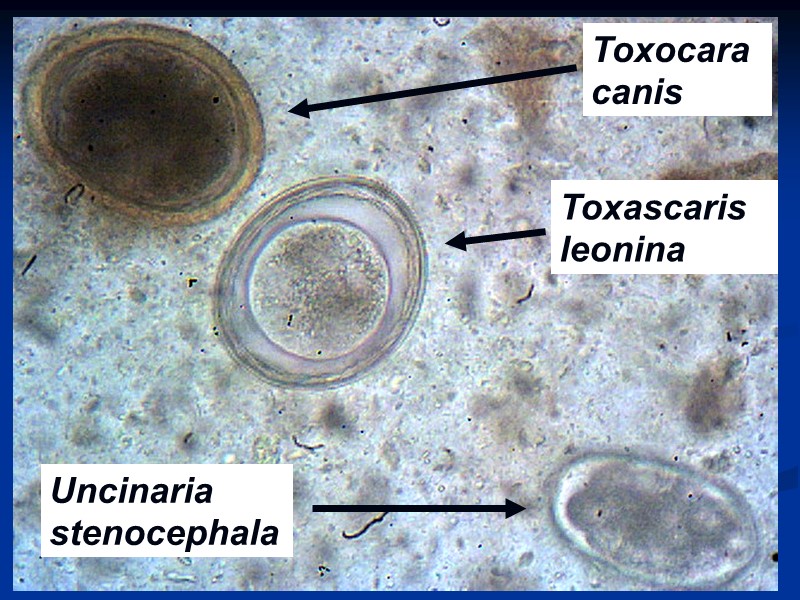

Микрофотографии яиц гельминтов Toxocara canis

Раздел: Фотоэссе